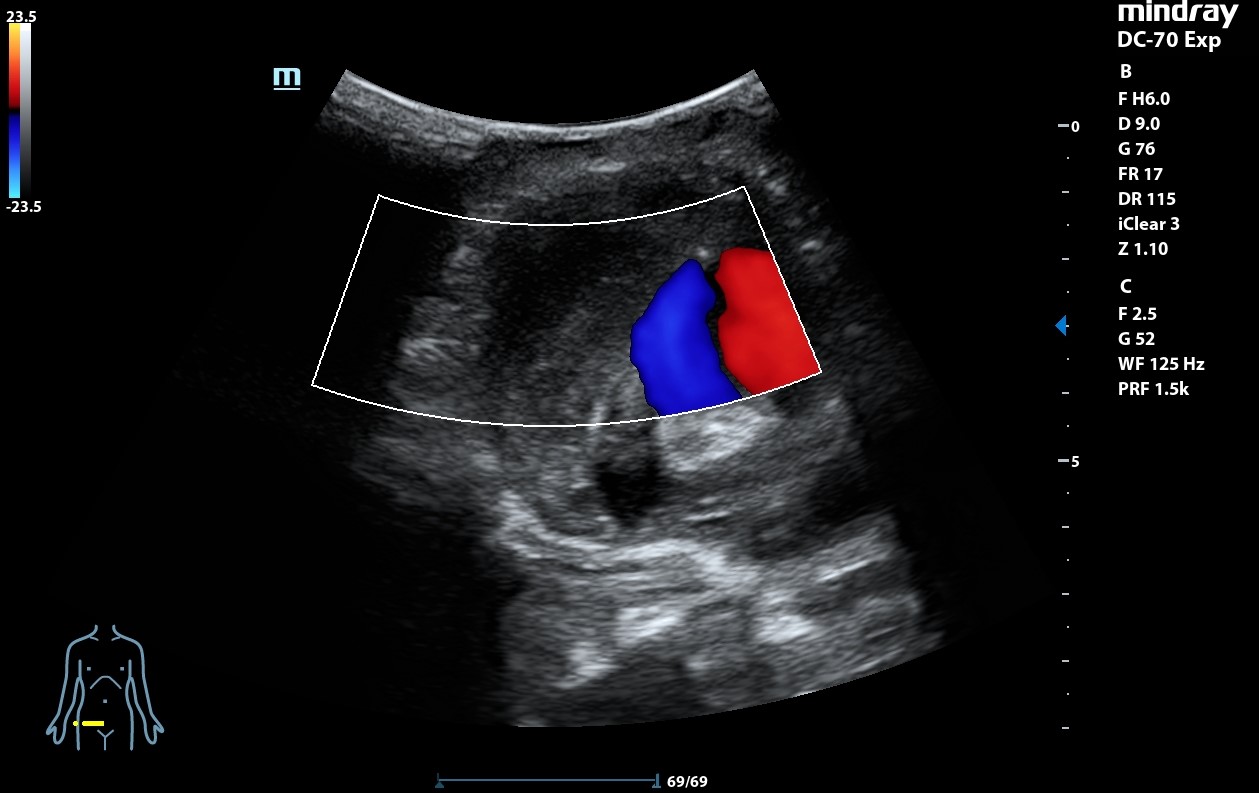

Ecografía clínica: arteria femoral dilatada con material hipoecoico heterogéneo en su pared lateral con un diámetro de 5,85 x 5,88 cm. Dilatación de aorta infrarrenal de 5,1 cm.

Diagnóstico: Aneurisma de arteria femoral derecha. aneurisma de aorta.